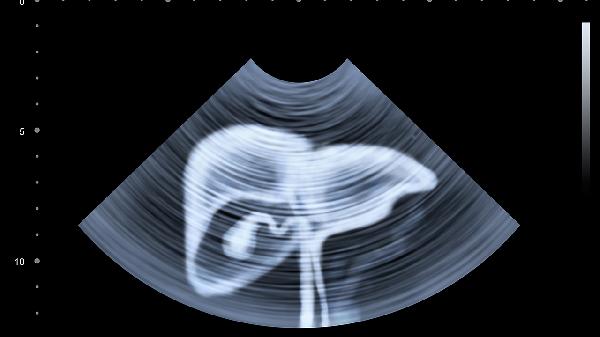

胆囊壁欠光滑是超声检查中常见的描述性术语,指胆囊壁回声不均匀或轻微增厚。生理状态下胆囊壁应呈现光滑均匀的线状高回声,欠光滑多与慢性炎症刺激有关。长期高脂饮食、胆汁淤积可能导致胆固醇结晶附着于胆囊壁,形成细微凹凸。轻度胆囊炎发作后,黏膜层水肿消退不完全也会遗留壁粗糙表现。这类情况通常无显著症状,可通过调整饮食结构、定期复查监测变化。

当胆囊壁欠光滑合并壁增厚超过3毫米、分层现象或血流信号增强时,需警惕病理性改变。急性胆囊炎发作期可见黏膜层断续不连续,化脓性感染会出现壁内小脓肿形成的虫蚀样改变。胆囊腺肌症表现为罗-阿氏窦扩张形成的壁内憩室,胆固醇息肉则呈现桑葚样突起。此类情况多伴随右上腹隐痛、餐后腹胀或脂肪泻等症状,需结合肿瘤标志物检查排除恶性病变可能。